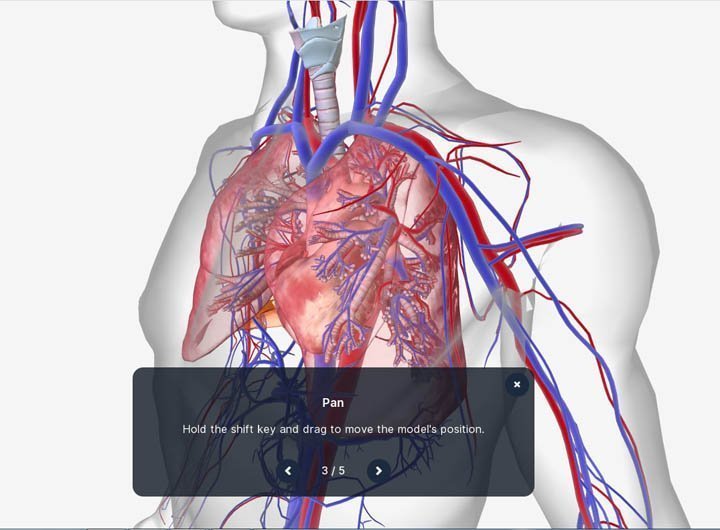

મોબાઇલ કે પીસીમાં human.biodigital.com સાઇટ પર, કોઈ પણ સિસ્ટમ ઓપન કર્યા પછી, માઉસથી ક્લિક-ડ્રગ કરીને કે આંગળીથી એનેટોમીનો વ્યૂઇંગ એંગલ બદલી શકાશે.

મોબાઇલ કે પીસીમાં human.biodigital.com સાઇટ પર, કોઈ પણ સિસ્ટમ ઓપન કર્યા પછી, માઉસથી ક્લિક-ડ્રગ કરીને કે આંગળીથી એનેટોમીનો વ્યૂઇંગ એંગલ બદલી શકાશે.

આખેઆખી એનેટોમીની જગ્યા બદલવી હોય, તો પીસીમાં શિફ્ટ કી પ્રેસ કરી, માઉસથી ડ્રેગ કરો. મોબાઇલમાં એક સાથે બે આંગળીથી ડ્રેગ કરીને એનેટોમીની પોઝિશન બદલી શકાશે.

આખેઆખી એનેટોમીની જગ્યા બદલવી હોય, તો પીસીમાં શિફ્ટ કી પ્રેસ કરી, માઉસથી ડ્રેગ કરો. મોબાઇલમાં એક સાથે બે આંગળીથી ડ્રેગ કરીને એનેટોમીની પોઝિશન બદલી શકાશે.